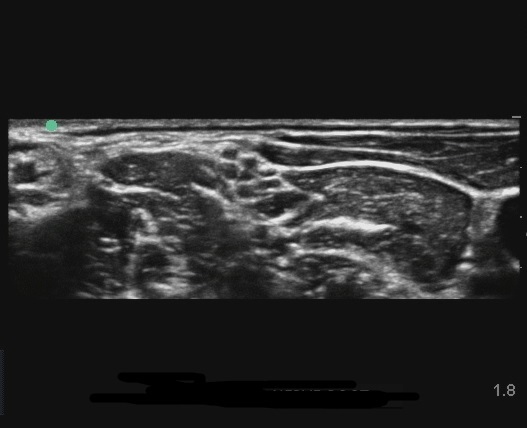

EDGE:肌间沟